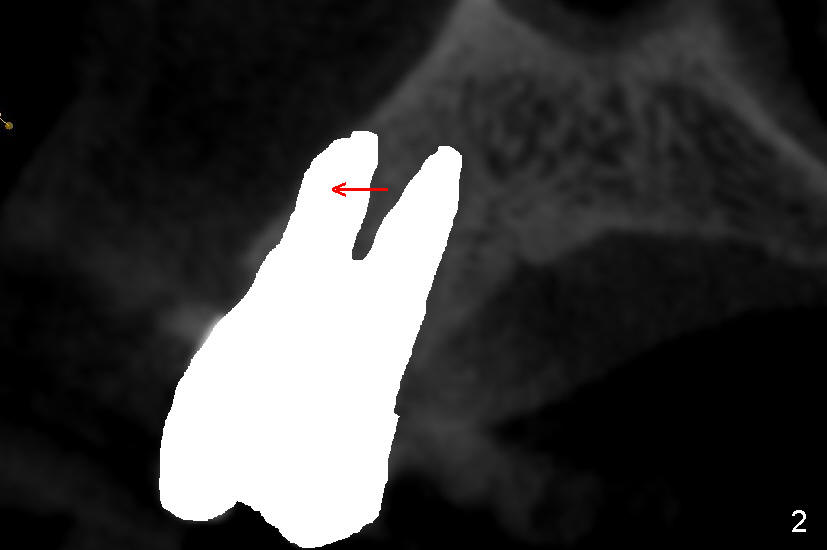

It is known that that buccal wall (apical) of anterior teeth including bicuspids is thin (Fig.1 between arrowheads). Fig.1 is a CT coronal section of an upper first bicuspid, whereas Fig.2 is a diagram showing after extraction. We are going to show how immediate implantation is to push the septum buccally (arrow) to close the buccal apical defect.